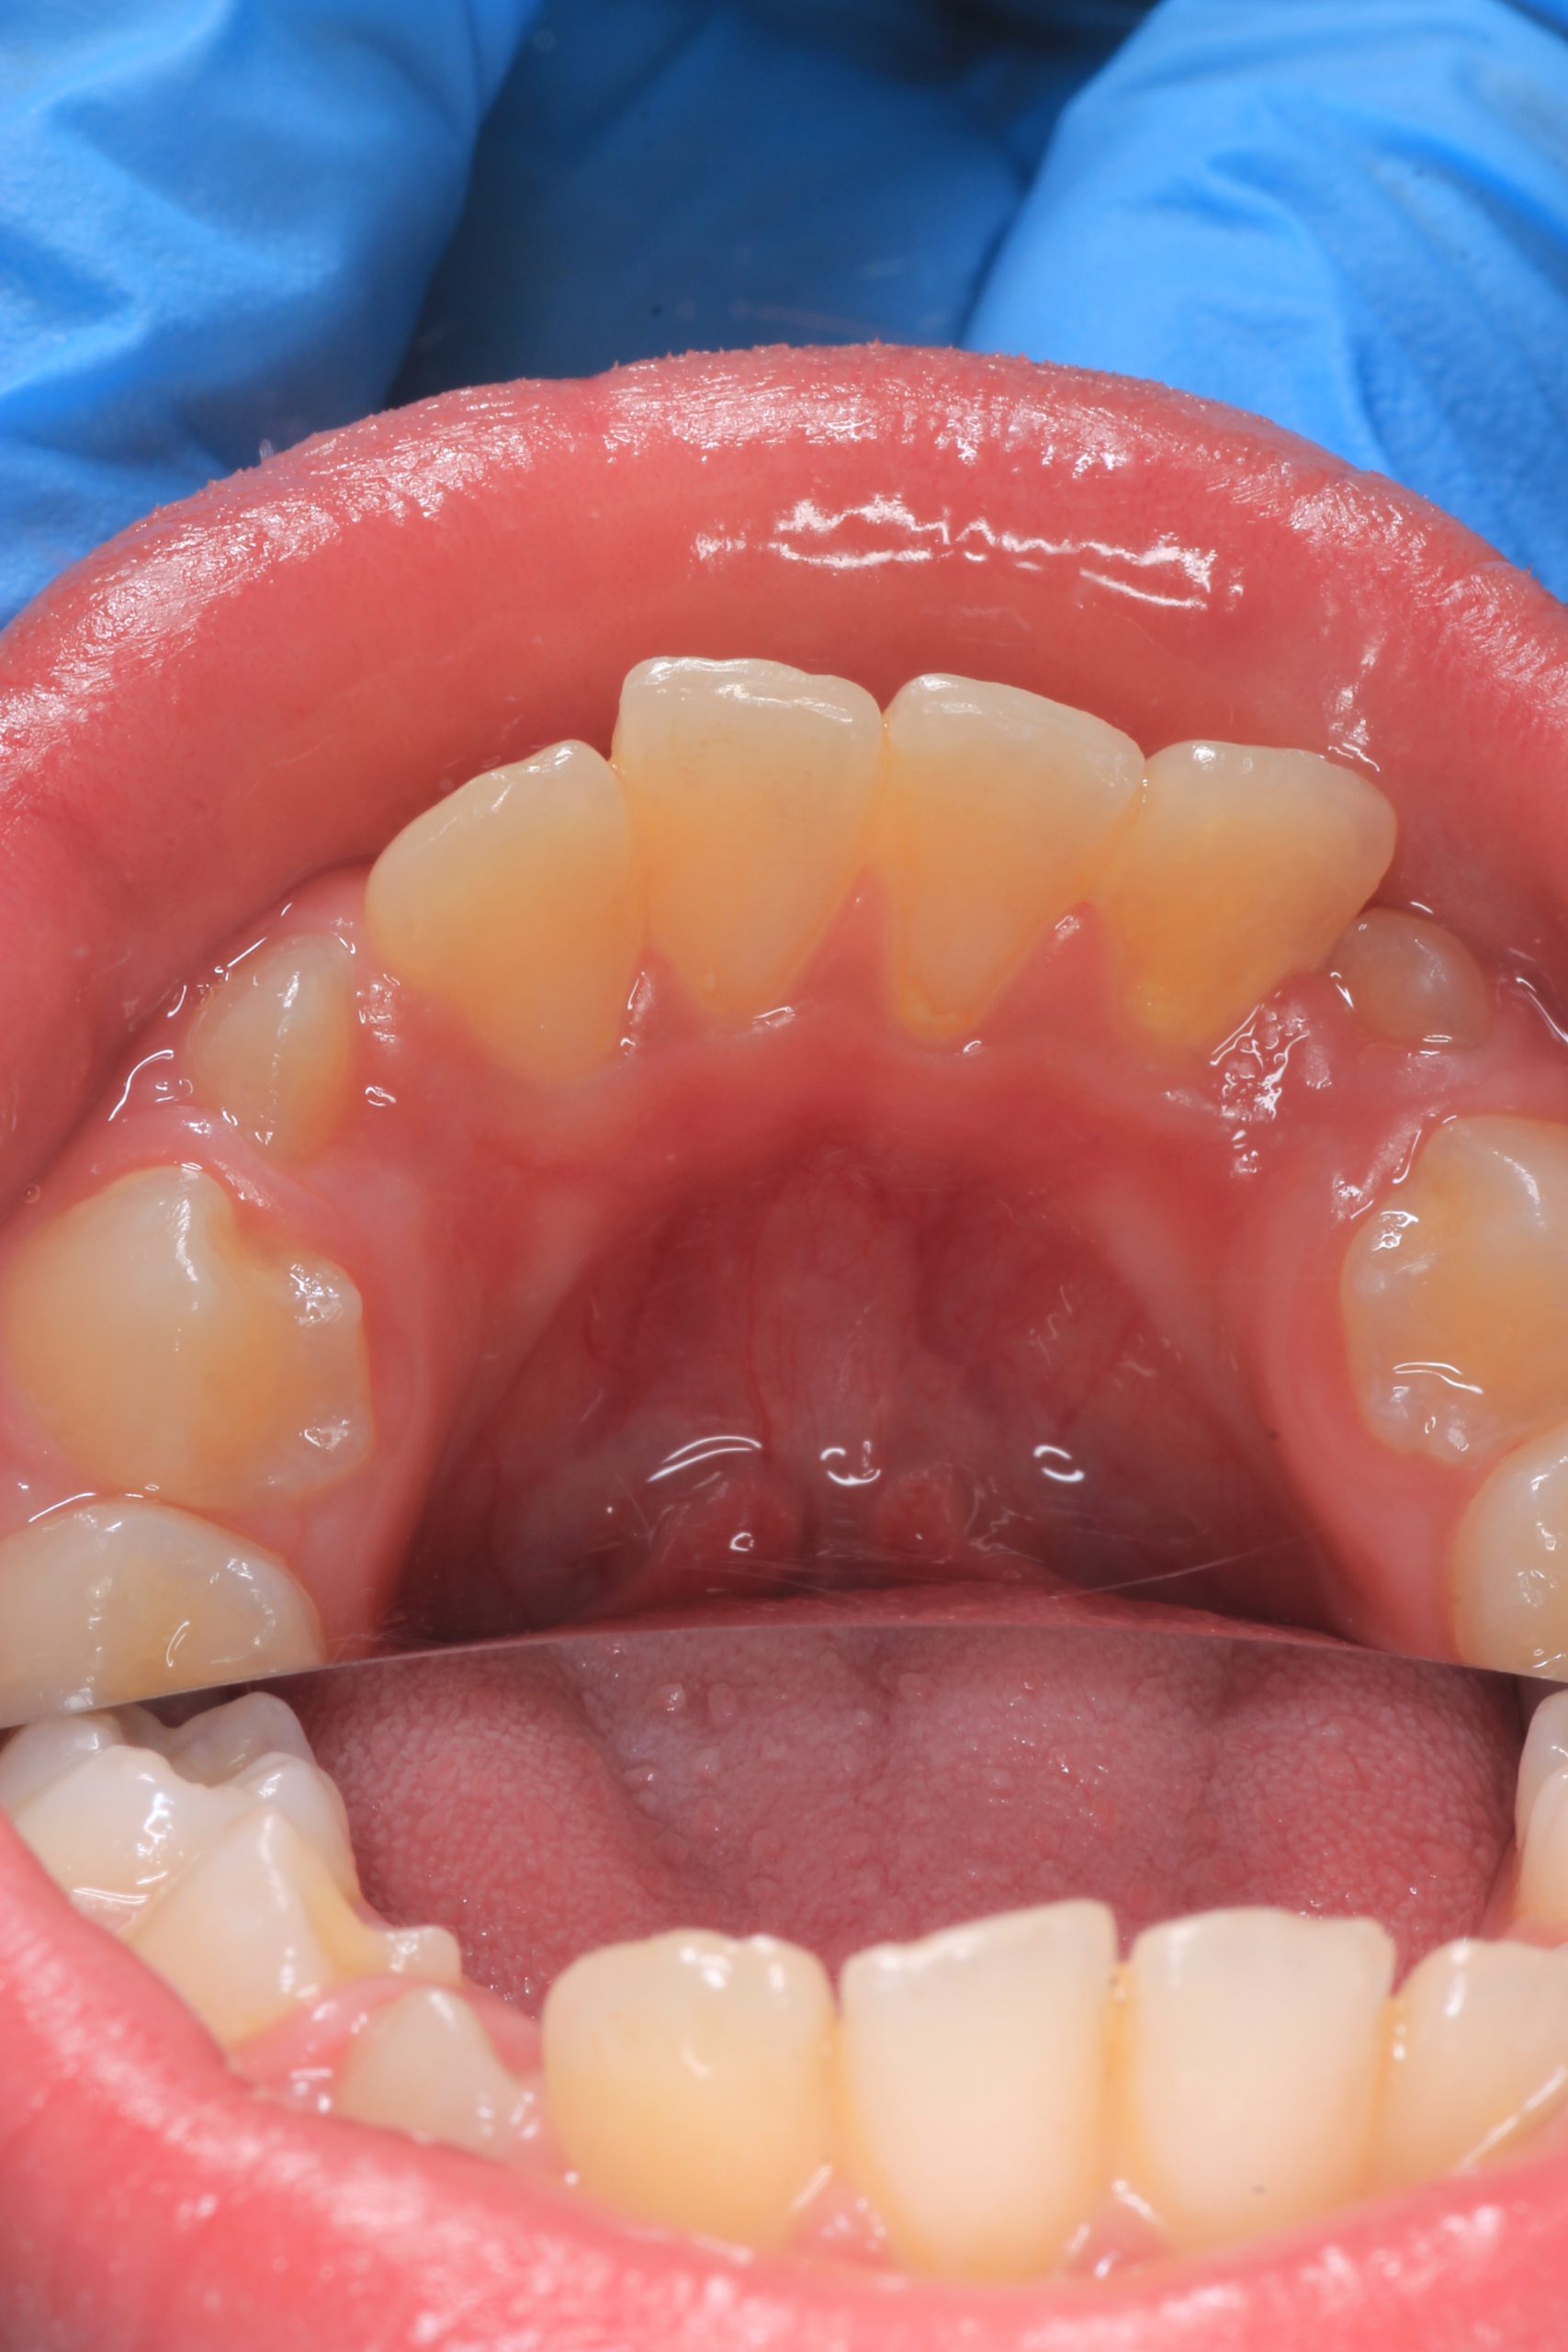

Together with your child, we practice brushing techniques, correct mistakes, and provide personalized recommendations. We advise whether to use manual or electric brushes, floss, interdental brushes, or remineralizing gels. - Plaque Removal with AIRFLOW Prophylaxis Master (EMS, Switzerland)

From age 4–5 and up, we perform full GBT cleaning using an ultra-fine erythritol powder to clean even hard-to-reach areas gently and safely. It does not damage enamel and is ideal even around braces — no need to remove brackets or wires. - Tartar Removal (If Needed)